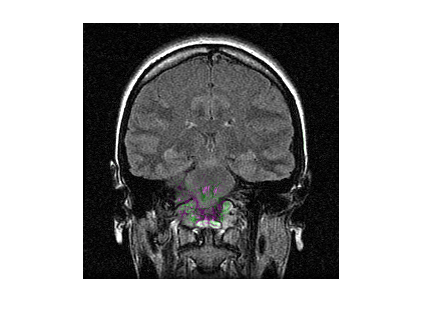

Load a MAT file containing a reference volume into the workspace. Convert the reference volume to data type double.

load mristack.mat

fixed = im2double(squeeze(mristack));Create a deformed volume using local transformations.

local = fixed(160:200,100:140,:); local = imrotate(local,90); moving = fixed; moving(160:200,100:140,:) = local;

Display a slice of the fixed volume and a corresponding slice of the moving volume. Observe the deformation in the alignment of the volumes.

figure imshowpair(fixed(:,:,10),moving(:,:,10))

Register the moving volume to the fixed volume.

[dispField,reg]=imregdeform(moving,fixed,GridRegularization=0.001);

Display the same slice of the fixed volume and the corresponding slice of the registered volume. Observe the improved alignment of the volumes.

figure imshowpair(fixed(:,:,10),reg(:,:,10))